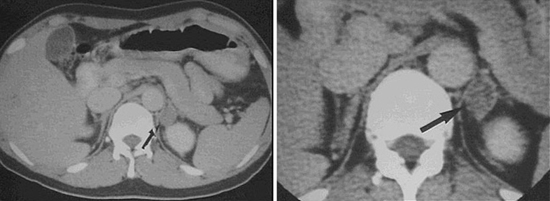

복부 전산화단층촬영(CT)은 현재 부신의 영상학적 검사에서 가장 먼저, 그리고 가장 많이 사용되는 검사방법입니다. 부신 종양의 크기, 모양, 주변으로의 침윤 정도를 비교적 정확하게 확인할 수 있습니다. 부신암이 확진되면, 전이 여부를 평가하기 위해 흉부 전산화단층촬영 등을 추가로 시행하여 부신 이외의 다른 장기들로의 원격 전이 등을 평가합니다.

[ 부신 종양에 대한 전산화단층촬영 ]